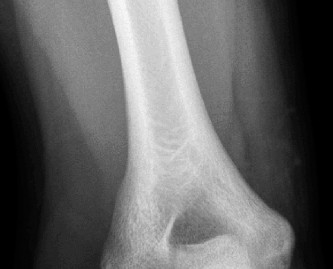

A 16-year-old male baseball player presents to your office for evaluation of his worsening right elbow pain. …